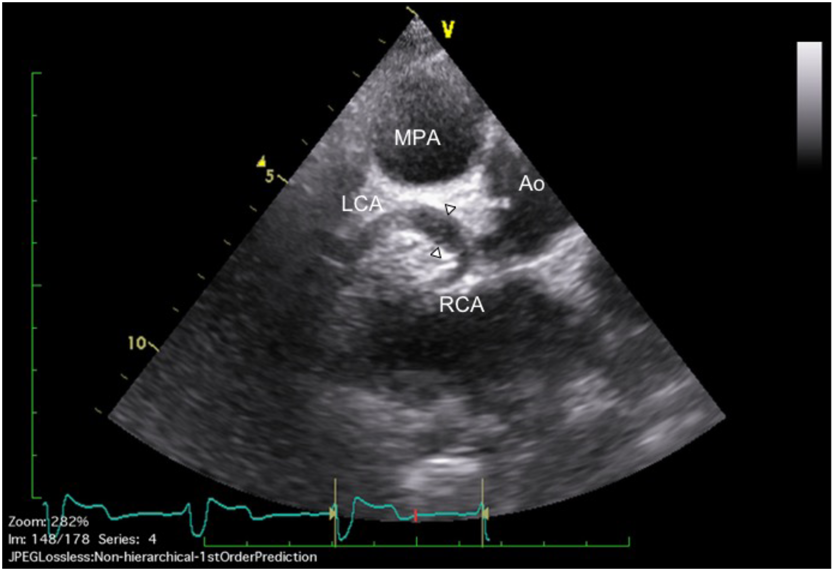

左単一冠動脈の拡張を伴い,SHOC2遺伝子異常が認められたNoonan症候群の1例A Case of Noonan Syndrome with the SHOC2 Mutation Complicated by Dilation of a Single Left Coronary Artery